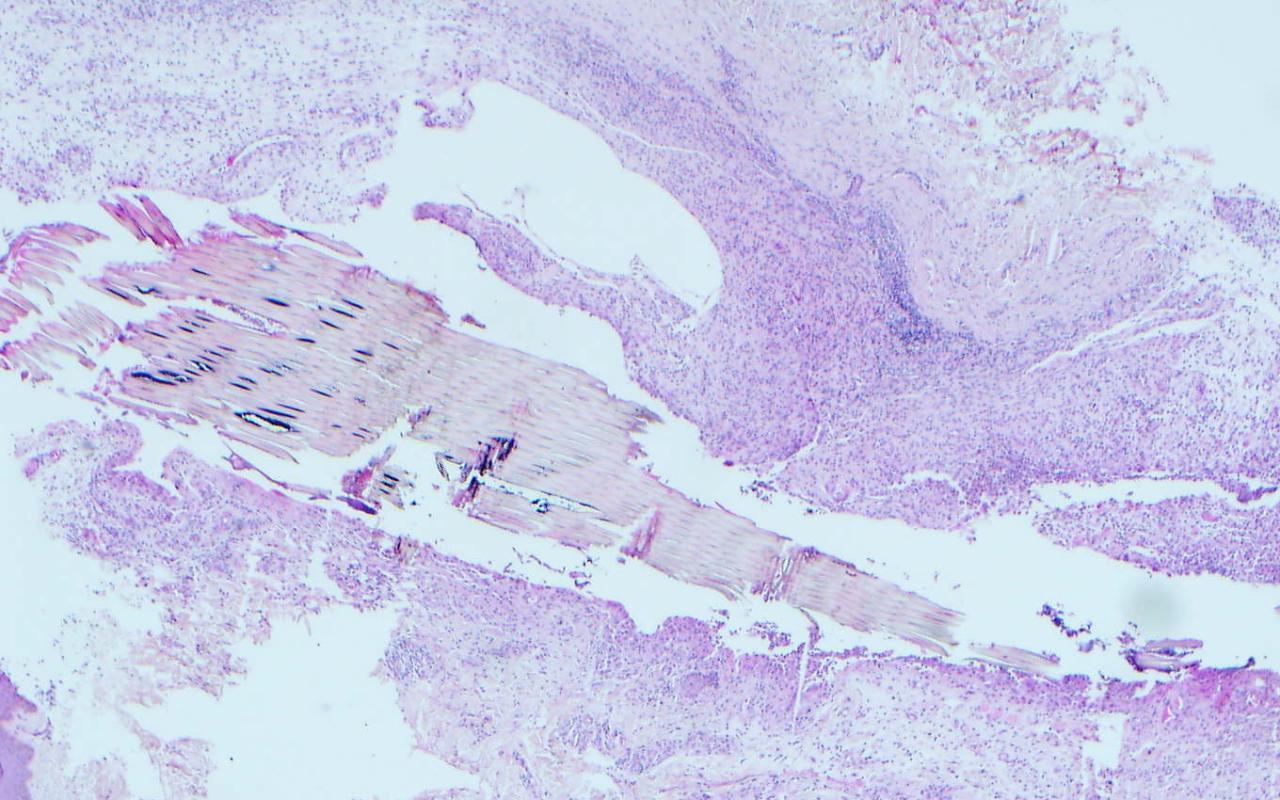

Correct choice:A. Wood splinter

Explanation: Wood splinter is brown with rectangular cells. Suture is typcially a circle filled with many smaller circles. Silicone is a collection of vacoules. Gel foam is an irregularly shaped purple mass. Hyaluronic acids are just like mucin wispy and purple collections.